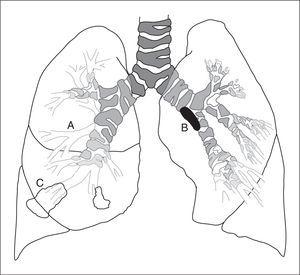

Figura 2.Esquema que muestra la diferente localización en que se realizaA)la biopsia de la mucosa bronquial en una carina segmentaria o subsegmentaria,B)la biopsia bronquial de una lesión endobronquial, yC)la biopsia transbronquial o biopsia pulmonar broncoscópica en posición subpleural.

Biopsia bronquial

El término biopsia bronquial o biopsia endobronquial engloba el análisis microscópico de lesiones endobronquiales y de la mucosa bronquial (fig. 2). En este último caso se incluye habitualmente el epitelio, la membrana basal y, con menos frecuencia, el músculo liso66.

Figura 2.Esquema que muestra la diferente localizaciónen que se realizaA)la biopsia de la mucosabronquial en una carina segmentaria o subseg-mentaria,B)la biopsia bronquial de una le-sión endobronquial, yC)la biopsia transbron-quial o biopsia pulmonar broncoscópica enposición subpleural.

Biopsia transbronquial

La biopsia transbronquial o biopsia pulmonar broncoscópica constituye un método relativamente no invasivo y seguro de obtener parénquima pulmonar para su estudio, pudiendo evitar la necesidad de realizar una toracotomía77,78 (fig. 2).